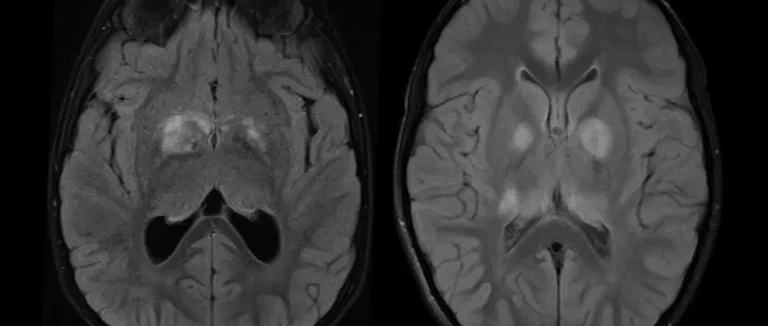

Современные методы визуализации

Современные методы визуализации очень важны. Мы используем МРТ и КТ для получения детальных снимков мозга. Эти снимки помогают нам увидеть размер, форму и местоположение опухоли.

МРТ | Магнитно-резонансная томография | Детальные изображения мозга, определение размера и местоположения опухоли |

КТ | Компьютерная томография | Быстрая диагностика, оценка состояния мозга |